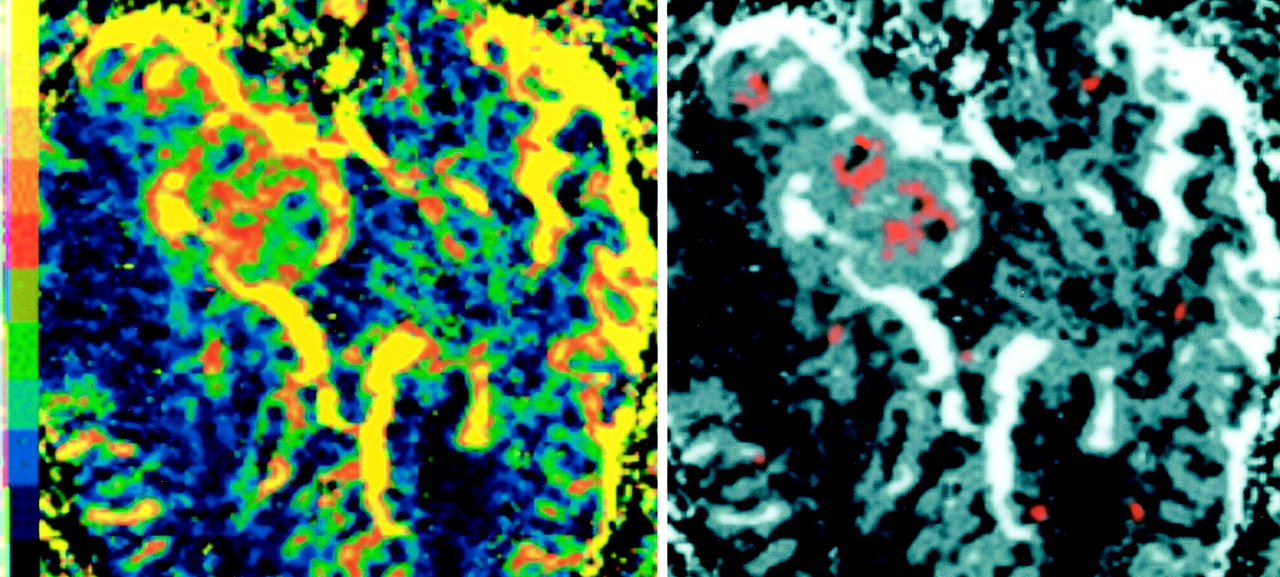

Dynamic images showed no evidence of significant motion during data acquisition in any case, and parametric images of rCBV and rR were of high quality (Fig 1). Measurements of mean rCBV (in arbitrary units) from the VOI ranged from 102 to 3256 with a group mean of 1678. The range of measurements for the mean rR was 0.076–0.257 with a group mean of 0.156. In normal tissue, values of rR exceeded 0.35 in 5% of pixels and 0.46 in fewer than 2%. Elevated values of rR above these thresholds were seen in two of the three grade II tumors with 7% and 9.6% of pixels above 0.35 and less than 1% of pixels above 0.46. Elevated values of rR were seen in all grades III and IV tumors with 9–21% of pixels above 0.35 and 8–12% above 0.46. Elevation of rR was most commonly seen in the central area of the tumors and adjacent areas of central necrosis, as previously described (16). The frequency of elevated values in grade II tumors was not significantly different than that of values in normal gray and white matter. Values in grades III and IV tumors were significantly greater than in grade II tumors and normal tissue (P < .01). No significant difference in the prevalence of elevated values existed between grades III and grade IV tumors.

Parametric images of rCBV (left) and rR (right) in a patient with glioblastoma multiforme. The rCBV map is in color to aid interpretation. The color scale is nonlinear: black, ≤2%; blue, 2–5%; green, 5–10%; red, 10–30%; orange, 30–80%; and yellow, ≥80%. The image demonstrates large peripheral vessels (yellow) and a central area of high rCBV within the tumor core (red) and other central areas of poor perfusion or necrosis (black). The red areas in the rR map indicate pixels with values <0.46, which are seen in fewer than 2% of normal tissue. Single-pixel areas of elevated rR have been filtered out, and the pixel clusters have been filtered by using a 0.5-pixel gaussian filter. The underlying gray-scale image shows the rCBV map. This image demonstrates areas of elevated rR, which occur principally in the center of the tumor, adjacent to areas of necrosis and away from the central area of elevated rCBV.

Abnormalities in the recirculation phase of the contrast agent bolus also offer the possibility of further characterizing the neoangiogenic microvasculature. The angiogenic process is stimulated by regional hypoxia and hypoglycemia (3); thus, cytokine production is most active in areas of the tumor subject to hypoperfusion and ischemia. In rapidly growing tumors such as glioblastoma multiforme, the angiogenic activity is unable to provide adequate perfusion, and necrosis occurs in central areas of the tumor. The areas of most active angiogenic cytokine production are characterized by inadequate perfusion, and capillary blood flow is likely to be slow and erratic (27). These flow characteristics will give rise to the abnormalities in the recirculation phase of the contrast agent bolus, which we have demonstrated herein and in previous work (16). The rR parameter therefore can indicate these areas of inadequate and deranged flow that likely exist deep in the tumor and adjacent to areas of necrosis. The finding of these abnormalities is likely to indicate a rapidly growing, aggressive tumor in which the angiogenic process is failing to adequately support tumor demands. These hypotheses are supported by the finding of elevated areas of rR centrally within glioblastomas in areas adjacent to regions of necrosis ([16] and Fig 1) and by the observation in this study that elevation of rR is seen only in grade III and IV tumors.